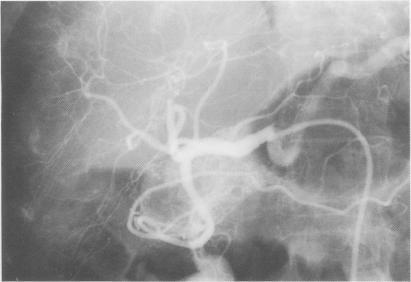

Gastric antral vascular ectasia ('watermelon stomach') is a rare cause of chronic gastrointestinal bleeding and various medical and surgical treatments have been described. We report a patient in whom an oestrogen-progesterone preparation successfully controlled recurrent blood loss.